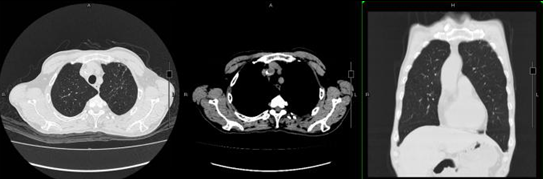

• 5月10日复查胸部CT:左上肺动脉、前段动脉及右下肺动脉、后外基底段动脉附壁血栓形成,与前大致相仿;左肺上叶尖后段炎症并空洞形成,较前有所吸收好转;左肺下叶舌段炎症较前有所吸收好转(图4)。患者体温稳定,血象好转。

图4  患者胸部CT(2018年5月10日)

注:5月10日复查CT示左肺上叶炎症并空洞形成较前有所吸收好转

• 8月3日复查胸部CT示左肺上叶空洞完全消失(图5)

图5  患者胸部CT(2018年8月3日)

注:胸部CT示左肺上叶空洞完全消失